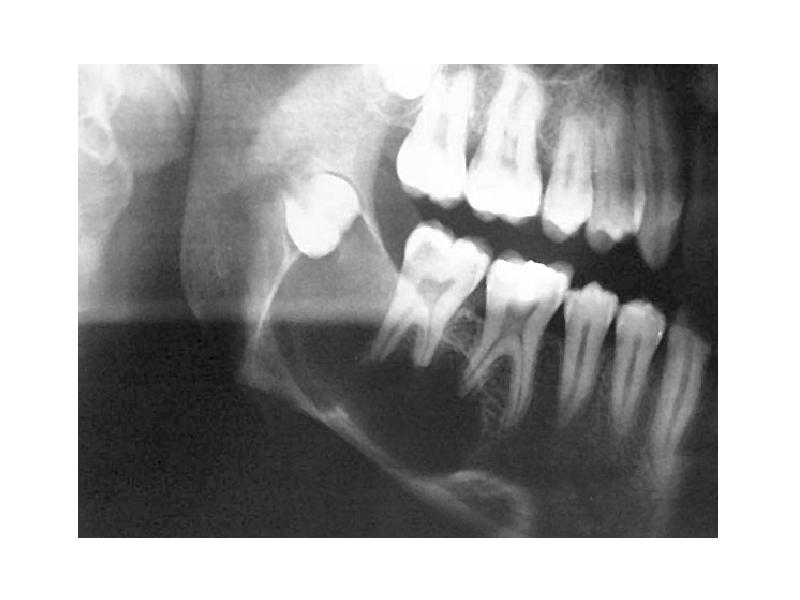

- 10. Амелобластома Доброкачественная опухоль с медленным, местнодеструирующим ростом В 80% тело нижней

- 11. Макроскопическая картина Пораженная челюсть веретенообразно утолщена ("вздутие"), при разрушении кортикальной пластинки

- 21. Макроскопическая картина Локализуется чаще всего в зоне формирующегося зачатка 3-го нижнего